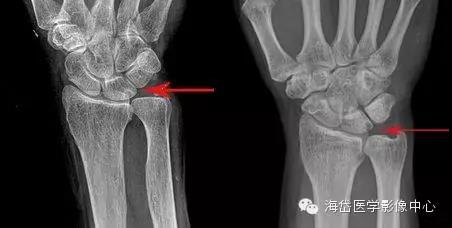

①X线:尺骨阳性变异(尺骨远端伸长)或处于中立位;月骨、三角骨坏死呈低密度小囊状改变以及月骨、三角骨关节面下软骨硬化,病变部位位于月骨尺侧近端和三角骨的腰部;尺骨小头相对关节面下软骨硬化或小囊性变。

其他X线表现包括桡骨远端骨折畸形愈合,桡骨远端异常背倾畸形和桡骨近端骨折畸形愈合导致桡骨缩短,尺桡远侧关节脱位。因为尺骨头与月骨解剖位置邻近,易发生撞击且易形成桥连状态(尺骨头与月骨连接)而产生持久性压迫,因此在尺骨阳性变异的患者中月骨发病率明显大于三角骨。

X线测量:在标准后前位X线平片测量尺骨变异,采用Gelberman等的平行线法(尺骨头关节面的平行线与乙状切迹最远端关节面的平行线之间的位置距离差)。

- 尺骨头长于桡骨为阳性变异;

- 尺骨头短于桡骨为阴性变异;

- 两者相等为中性变异。

对症状较重者、常规X线后前位显示尺骨变异呈阴性或中性者,采用握拳、腕旋前位摄片。